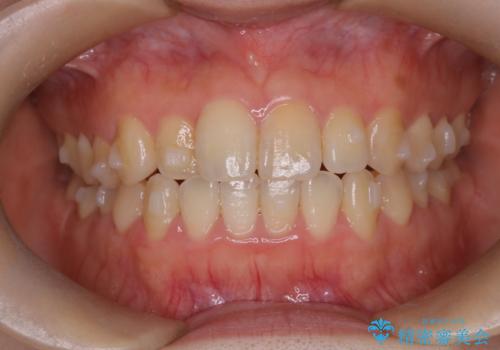

【インビザライン】前歯のがたつきを目立たない装置で治療

- 前歯の叢生を主訴に来院されました。目立たない装置を希望されたためインビザラインで治療を行いました。

IPRと拡大をし、叢生を治しました。右上2番は反対咬合でしたが短期間できれいに治りました。